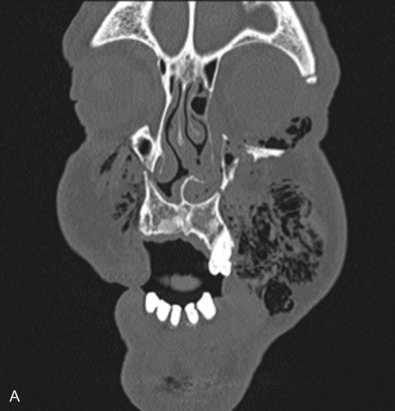

The gold standard for radiographic evaluation is thin-slice helical computed tomography (CT). Midface fractures are confirmed by axial, coronal, and sagittal views. The degree of comminution, bone loss, and detailed images of the fracture patterns can be assessed and juxtaposed to surrounding soft tissue structures. 3D reconstruction, when utilized, can aid in visualizing the complex 3D anatomical orientation of fracture fragments that occur in Le Fort injuries and facilitate reconstructive planning.

Classification

Le Fort I pattern fractures are characterized by a transverse fracture extending from the pyriform aperture, propagating laterally across the maxillary wall involving medial, anterior, and lateral components, and ending posteriorly at, or through, the level of the pterygoid plates ( Figs. 1.13.11–1.13.13 ). This results in mobilization of the lower third of the midface, whilst the upper two-thirds remains intact. The force is typically delivered above the maxillary teeth, causing a palatal/alveolar separation from the upper maxilla.